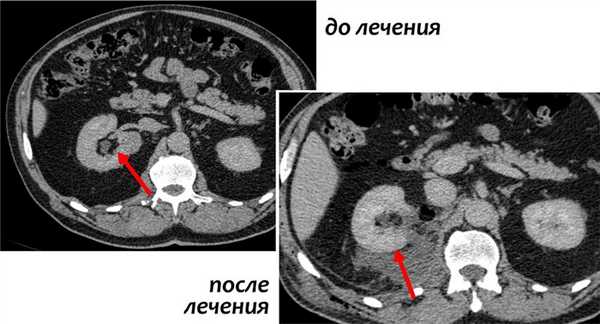

3D-реконструкции опухоли Вильмса пациентов детского отделения НМИЦ онкологии им. Н.Н. Петрова

Опухоль Вильмса. Компьютерная томография